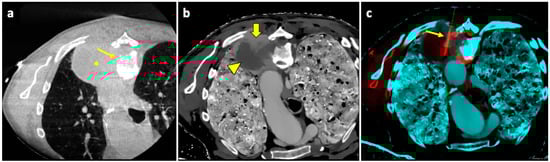

A useful technique in this setting is fusion imaging, which is defined as the process of overlapping imaging datasets from different modalities into a single composite imaging dataset. By using dedicated software, it is possible to overlap pre-procedural 18F-FDG PET/CT images to intra-procedural CBCT images, thus integrating functional and anatomical data, and to guide the needle towards the viable and metabolically active portion of the target lesion. An example of a biopsy guided by fusion imaging between CBCT and PET-CT is illustrated in Figure 5.

It has been demonstrated that the technique is effective [133], increasing the chances of obtaining diagnostic samples while performing fewer biopsies, improving the quality of histological analysis [134].

An example of a biopsy guided by fusion imaging between pre-procedural spectral CT and intra-procedural CBCT is illustrated in Figure 6.